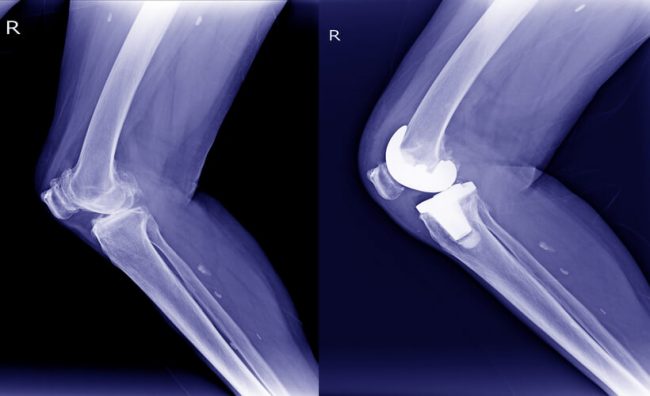

Canarias ha dado un paso histórico en el campo de la rehabilitación y la cirugía protésica: la implantación de la primera prótesis endoesquelética inteligente intervenida en España de la mano de los doctores José Luis Pais Brito y Pablo S. Coronas Pérez-Cardona.